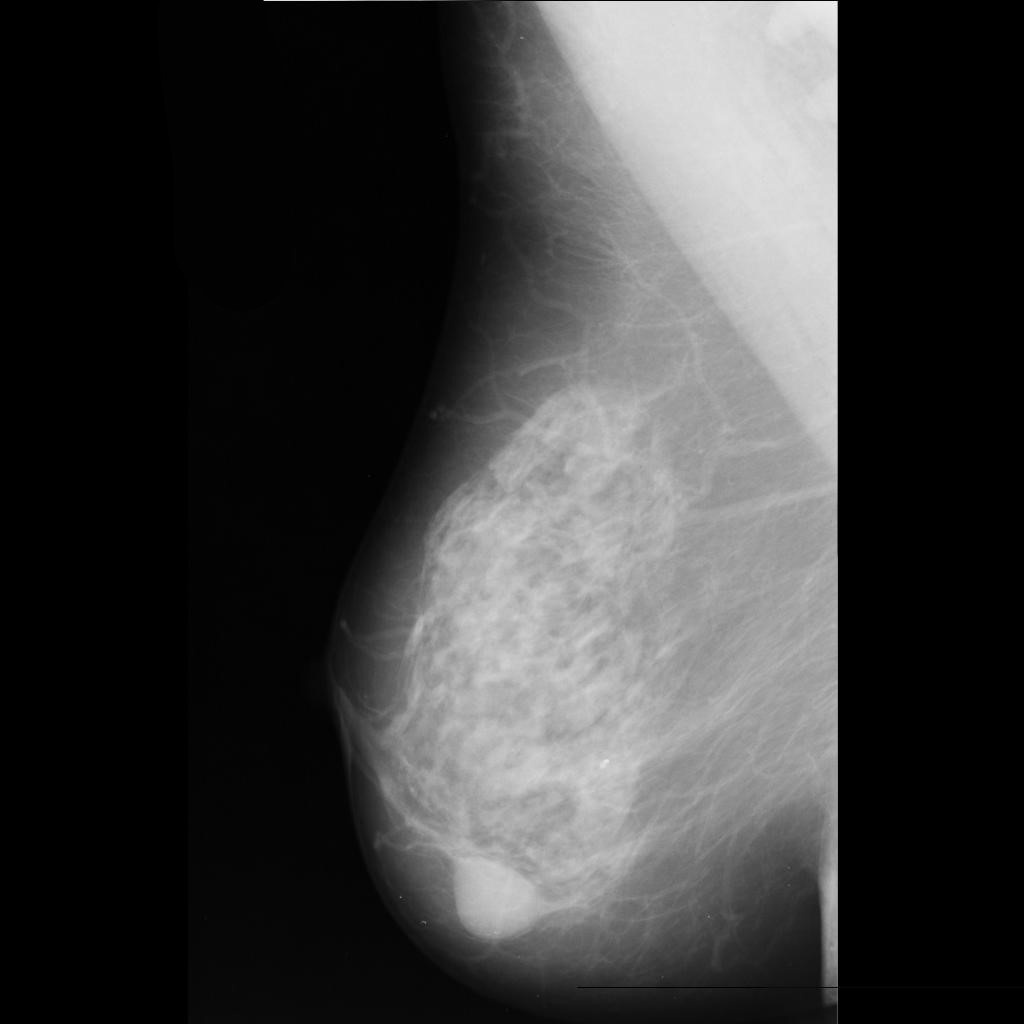

benign

malignant